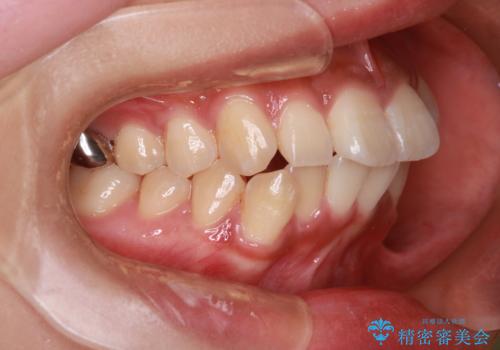

- 前歯の突出が強く、口元が前に出ている印象を改善するため、上下左右の第一小臼歯(4番)を抜歯する矯正治療を計画しました。抜歯により得られたスペースを利用して、前歯を後方へと移動させて整列します。治療には目立ちにくい透明な審美ブラケットとワイヤーを使用し、毎月1回の調整を行いながら徐々に歯を動かし、約2年で口元全体を整える計画としました。

前歯が前に出ているため口元が突出し、唇が閉じにくいなどの悩みを抱えておられました。治療にあたり上下左右の第一小臼歯を抜歯し、十分なスペースを作ることで前歯を効果的に後方へ移動させました。装置には透明で目立ちにくい審美ブラケットを採用し、治療中の審美的ストレスを軽減しました。定期的な調整を通じて無理なく確実に歯列を整え、前歯の突出感を解消。治療後は口元の印象が自然で美しく改善され、患者様には非常にご満足いただけました。